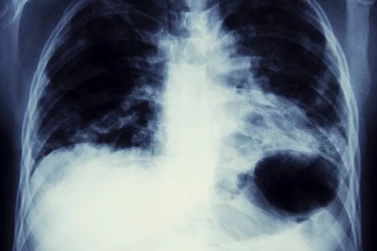

Inhalation of asbestos dust can increase the risk of developing lung cancer. If you or a family member has been diagnosed with lung cancer as a result of asbestos exposure, then you could be entitled to asbestos-related lung cancer compensation.

It can be difficult to prove that a client’s lung cancer is caused by exposure to asbestos because there are a number of other factors which can cause the disease, most commonly smoking.

However, if a lung cancer patient is already suffering from an asbestos-related disease, it is usually accepted by the legal and medical profession that the cancer was caused by asbestos. In other cases, there needs to be evidence of prolonged or heavy asbestos exposure in order to claim damages.

Generally, lung cancer symptoms include a long-term cough, being short of breath, a loss of appetite and weight loss. Lung cancer can be treated in a number of ways including chemotherapy, radiotherapy and surgery.